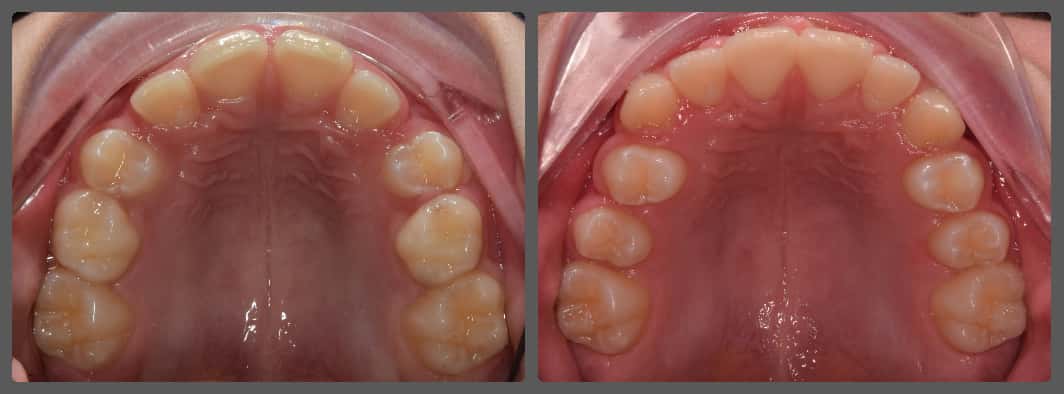

Bettinát a Semmelweis Egyetemen kezeltem, ahol az első fogszabályozási konzultáció alkalmával kiderült, hogy az enyhe torlódása mellé egy jelentős felső állcsontszűkület is társul. Jobb oldalon keresztharapás volt látható. A szűk felső fogív az alsó állkapocs kényszeres elcsúsztatását eredményezte, ami a jelentősen jobbra tolódott alsó középvonalon is jól látszik. A megfelelő diagnózis felállítása után két fázisú (előkezelés, majd rögzített készülékes kezelés) terápia mellett döntöttünk. Bettina kezelését az I. fázisban hyrax készülékkel kezdtük, ennek segítségével megtágítottuk a felső állcsontot, fogívet. A 8 hónapos I. fázist egy gyors, 14 hónapig tartó alsó-felső hagyományos rögzített készülékes kezelés követte. A fix készülékes kezelés során harapásemelőket és intermaxilláris gumihúzást is alkalmaztam a tökéletes végeredmény elérése érdekében. A két fázisú kezelés 22 hónapig tartott. Bettina folyamatos, töretlen együttműködésének köszönhetően úgy hiszem, hogy különösen szép végeredményt értünk el esztétikai és funkcionális szempontból egyaránt.